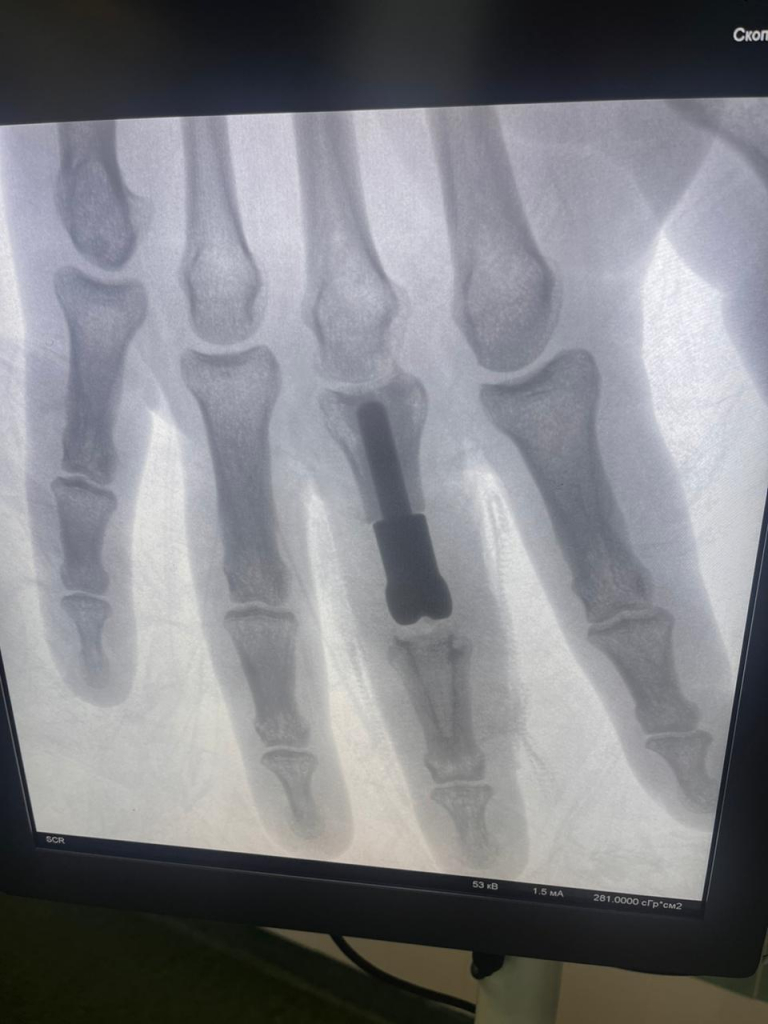

Врачи хирургического отделения Мытищинской областной клинической больницы провели пациенту с открытым оскольчатым внутрисуставным переломом среднего пальца правой руки эндопротезирование с применением аддитивных технологий. Об этом сообщили в пресс-службе медицинского учреждения. Это первая в Московской области операция подобного рода.

По данным медиков, пациент получил тяжелое повреждение, которое затронуло не только кости, но и межфаланговый сустав. Также были травмированы сухожилия, участвующие в разгибании пальца, и покровные ткани. В итоге врачи изготовили для пациента индивидуальный эндопротез, который не только заменил повреждённый сустав, но и восполнил дефект основной фаланги пальца.

По словам хирурга-травматолога Алексея Сизикова, высокотехнологичный имплант напечатали из титанового порошка на 3D-принтере.

«Полученная конструкция учитывала все малейшие нюансы и особенности, которыми должен обладать имплант, предназначенный для конкретного пациента. В России в настоящее время есть уже несколько биометрических лабораторий, которые занимаются подобной инновационной деятельностью. За точность размеров компонентов и их форму отвечал биоинженер. Задача хирургов заключалась в установке созданного эндопротеза и проведении пластики поврежденного сухожилия», – пояснил специалист.